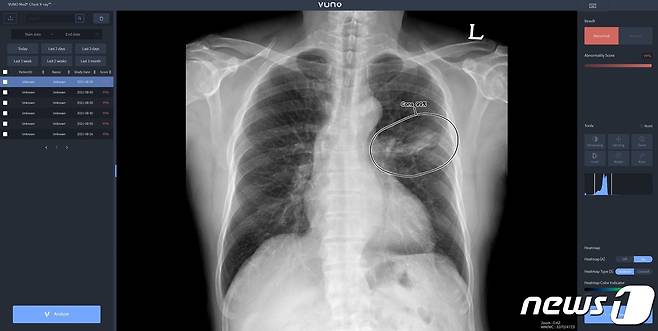

이번 계약으로 뷰노는 AI 기반 흉부 엑스레이 판독 보조 의료 소프트웨어 '뷰노메드체스트 엑스레이'를 디알젬에 공급한다.

이번 계약으로 뷰노는 AI 기반 흉부 엑스레이 판독 보조 의료 소프트웨어 ‘뷰노메드체스트 엑스레이’를 디알젬에 공급한다. 디알젬은 전체 엑스레이 장비 라인업에 뷰노의 AI를 기본 탑재해 국내와 해외 주요 국가에 판매할 예정이다.

뷰노메드스트 엑스레이는 흉부 엑스레이 영상에서 결절, 경화, 간질성 음영, 흉수, 기흉 등 주요 이상소견을 높은 정확도로 탐지하는 AI다. 의료진에게 이상소견의 소견명과 위치를 제시해 결핵, 폐렴 등 주요 폐질환 진단을 돕는다. 경량화된 모델로 개발돼 다양한 엑스레이 장비에 쉽게 연동할 수 있다.

계약에 따라 두 기업은 AI가 기본 탑재된 엑스레이 장비를 북미와 유럽, 중동 등 기존 디알젬의 글로벌 네트워크를 활용해 판매할 방침이다. AI가 탑재된 제품은 엑스레이 촬영과 동시에 AI로 분석된 결과를 한 번에 쉽게 확인할 수 있다. AI 활용 경험이 없는 국내외 신규 고객의 유입이 활발할 것으로 기대된다.